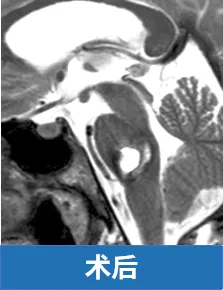

值得庆幸的是,巴特朗菲教授接手了这例高风险手术。在精细清除血肿及血管畸形的同时,特别注意保护脑桥后部实质及外展神经、面神经的完整性。术后一年随访显示,患者面神经和外展神经功能基本恢复,能自然露出真诚笑容。患者最终恢复至病前状态,曾经的恐惧感被稳定的踏实感取代。这完全得益于教授精湛的手术技术,将濒临危险的患者成功救治。